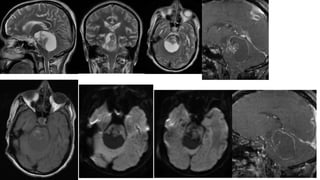

• Sagittal T1WI : Well-delineated,

lobulated pineal mass containing very

heterogeneous signa intensities. The

mass causing moderate obstructive

hydrocephalus.

• Sagittal T2WI : shows that the

heterogeneous appearing mass also

contains numerous cysts.

• Axial T1WI Shows T1 shortening

around the periphery of the mass

consistent with fat. The internal

signal void is caused by the densely

calcified component. A lobulated

mixed signal intensity component is

present in the posterior 3rd

ventricle.

• T1 C : Shows that the fat suppresses

and the lobulated component

enhances strongly.